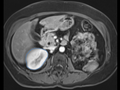

- Cardiac MRI Toolkit Tutorial Summer2013.pdf Pamin27

14:57, 21 August 2013

1,500 × 1,125, 41 pages; 2.4 MB